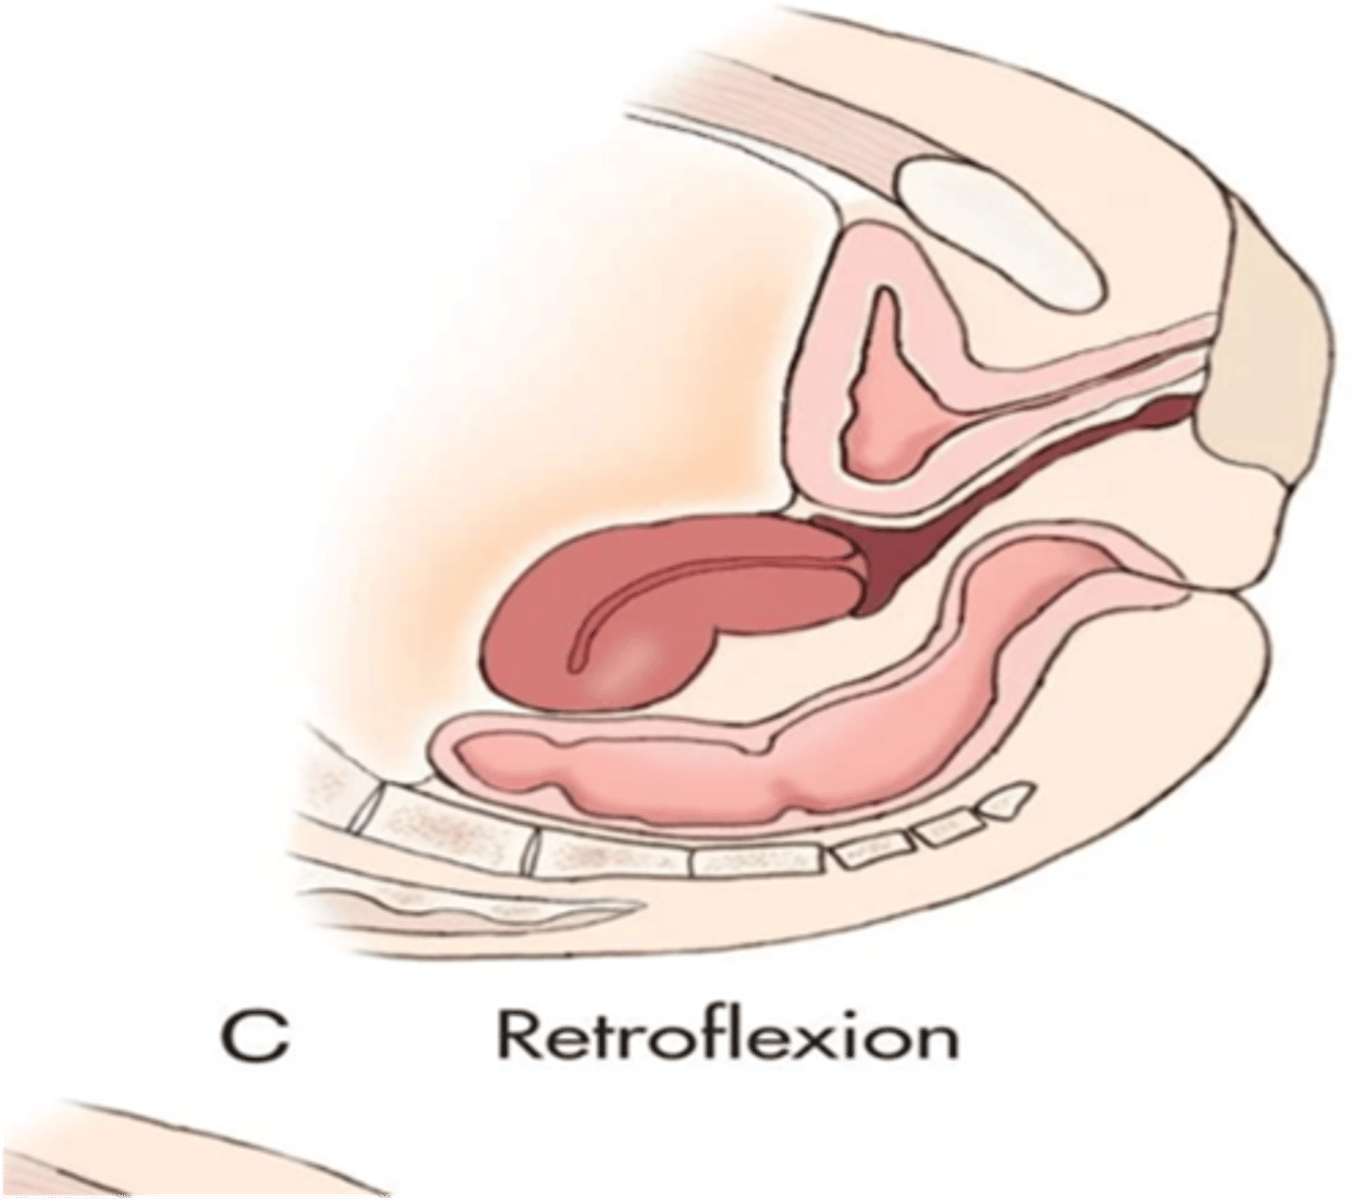

What is a retroflexed uterus?

body and fundus bend backward; fundus is adjacent to cervix and points down